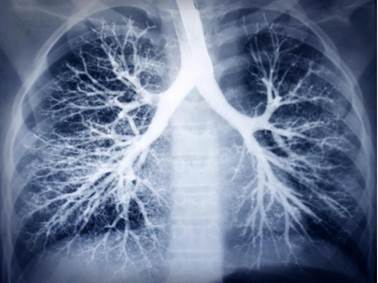

《国家年度报告:肺癌和黑色素瘤死亡率快速下降导致癌症死亡率总体持续下降》发布

2021年7月,《国家癌症状况年度报告》由美国癌症协会 (ACS)、疾病控制与预防中心 (CDC)、国家癌症研究所 (NCI)和北美中央癌症登记协会 (NAACCR)联合发布。报告指出,2001-2018年男性和女性的癌症死亡率下降速度都有所加快。男性的癌症死亡率从2001-2015年每年下降1.8%加速下降至2015-2018 年间每年下降 2.3%。女性的癌症死亡率从 2001 年到 2015 年每年下降 1.4% 加速下降至 2015-2018 年期间每年下降 2.1%。报告发现,2014-2018 年期间,每个种族和族裔的总体癌症死亡率都有所下降。另外,该报告指出,黑色素瘤死亡率大幅下降,但对于其他几种主要癌症,包括前列腺癌、结直肠癌和女性乳腺癌,之前死亡率的下降趋势已经放缓或消失。